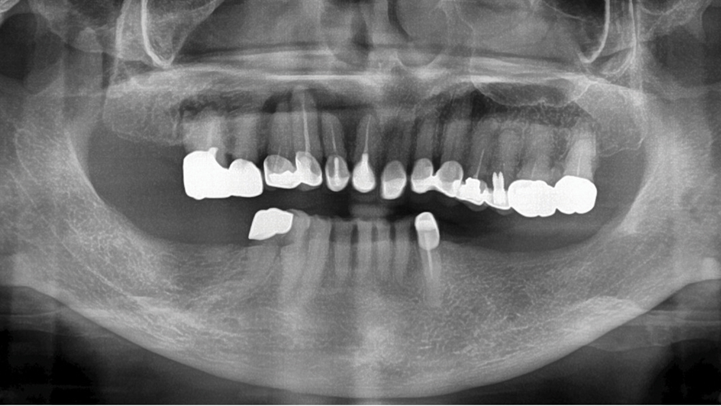

Clinical case: # 46 implant placement & GBR using i-Gen membrane for significant vertical resorption & mixed bone defect

- Courtesy of Dr. Iulian Filipov, Romania -